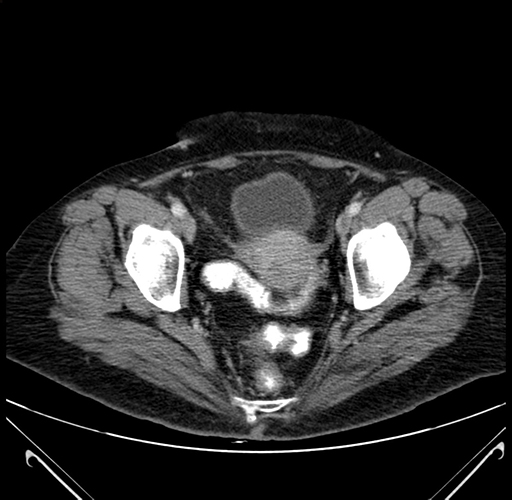

Pre-Chemo: Axial Venous

Axial Venous